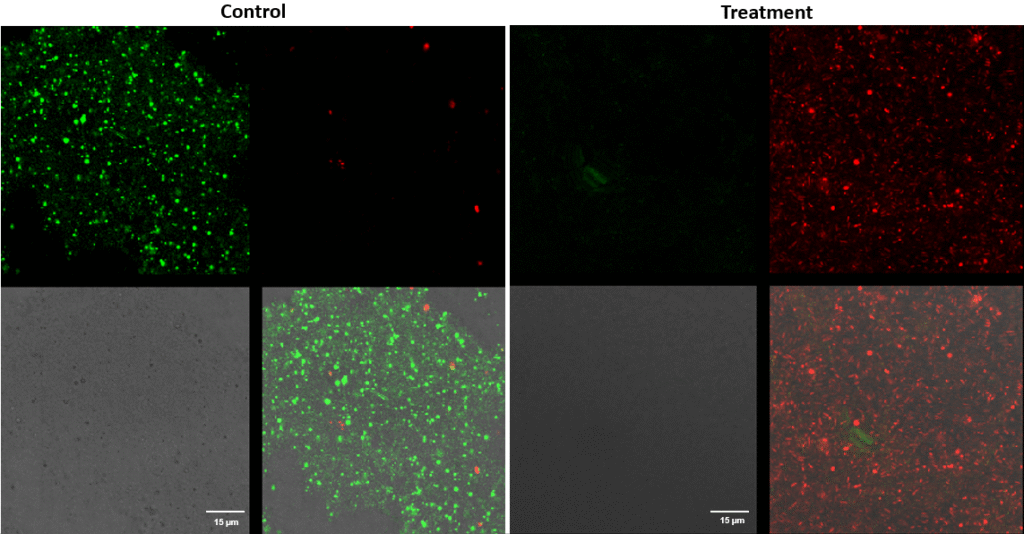

Streptococcus canis – Superficial fluorescence microscopy. Each image is divided into four quadrants: the upper left quadrant shows the green channel highlighting live bacteria; the upper right shows the red channel highlighting dead bacteria; the bottom right shows the merged green and red channels indicating live and dead bacteria; and the bottom left illustrates the bright field image. Bright green represents bacteria with intact membranes (live), red represents bacteria with compromised or dead membranes, and yellow represents bacteria with partially compromised membranes. Scale bar: 15 µm.

Pseudomonas aeruginosa – Superficial fluorescence microscopy. Microscopic imaging of Pseudomonas aeruginosa inoculated on the corneal surface and treated with UV-C for 15 seconds at a 10 mm distance. The images show clear bacterial membrane disruption and reduced viability, demonstrating the antimicrobial effectiveness of UV-C treatment on the superficial corneal layer.

Each image is divided into four quadrants: the upper left quadrant shows the green channel highlighting live bacteria; the upper right shows the red channel highlighting dead bacteria; the bottom right shows the merged green and red channels indicating live and dead bacteria; and the bottom left illustrates the bright field image. Bright green represents bacteria with intact membranes (live bacteria), red represents bacteria with compromised or dead membranes, and yellow represents bacteria with partially compromised membranes. Scale bar: 15 µm.